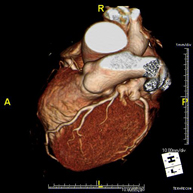

L'angio TC Cardíac o Coronariografia no invasiva és una prova diagnòstica que consisteix en l'estudi de les artèries del cor o artèries coronàries mitjançant l'ús d'un equip TC Multidetector d'última generació i de contrast iodat, i l'obtenció d'imatges bi i tridimensionals. El TC Multidetector o TCMD permet una adquisició d'imatges tan ràpida que es poden valorar les artèries coronàries amb alta precisió anatòmica: estrenyiment o estenosi, calcificacions, variants anatòmiques, etc. ja que gràcies a la seva rapidesa evita l'artefacte que provoca el moviment constant del cor (triga menys de deu segons en adquirir unes 1000 imatges). La informació obtinguda precisa un tractament en estacions de treball amb programes especialitzats en la reconstrucció de les artèries coronàries que permeten valorar el nombre, la localització i les característiques de lesions. Tota aquesta informació s'obté de manera no invasiva: només es requereix la punció d'una vena perifèrica (en el braç). És necessari que la freqüència cardíaca no superi els 75 batecs per minut per això alguns pacients hauran de realitzar un tractament previ amb un fàrmac betabloquejant. - PAAF (punció) de tòrax guiada per TC

L'Angio TC cardíac o la coronariografia no invasiva és una prova diagnòstica que consisteix en l'estudi de les artèries del cor o artèries coronàries mitjançant l'ús d'un equip de TC Multidetector d'última generació (64 corones o files de detectors) i de contrast iodat amb l'obtenció d'imatges bi i tridimensionals. El TC Multidetector 64 o TCMD64 permet una adquisició d'imatges tan ràpida que es poden valorar les artèries coronàries amb alta precisió anatòmica (estrenyiments o estenosis, calcificacions, variants anatòmiques, etc.), ja que, gràcies a la seva rapidesa, evita les falses imatges que provoca el moviment constant del cor (triga menys de deu segons en adquirir unes 1000 imatges). La informació obtinguda d'un tractament en estacions de treball amb programes especialitzats en la reconstrucció de les artèries coronàries que permeten valorar el nombre, la localització i les característiques de les lesions. Tota aquesta informació s'obté de manera no invasiva: només es necessita la punció d'una vena perifèrica (en el braç). És necessari que la freqüència cardíaca no superi els 75 batecs per minut, per això els pacients han de realitzar un tractament previ amb un fàrmac betabloquejant. - Angio TC d'aorta abdominal